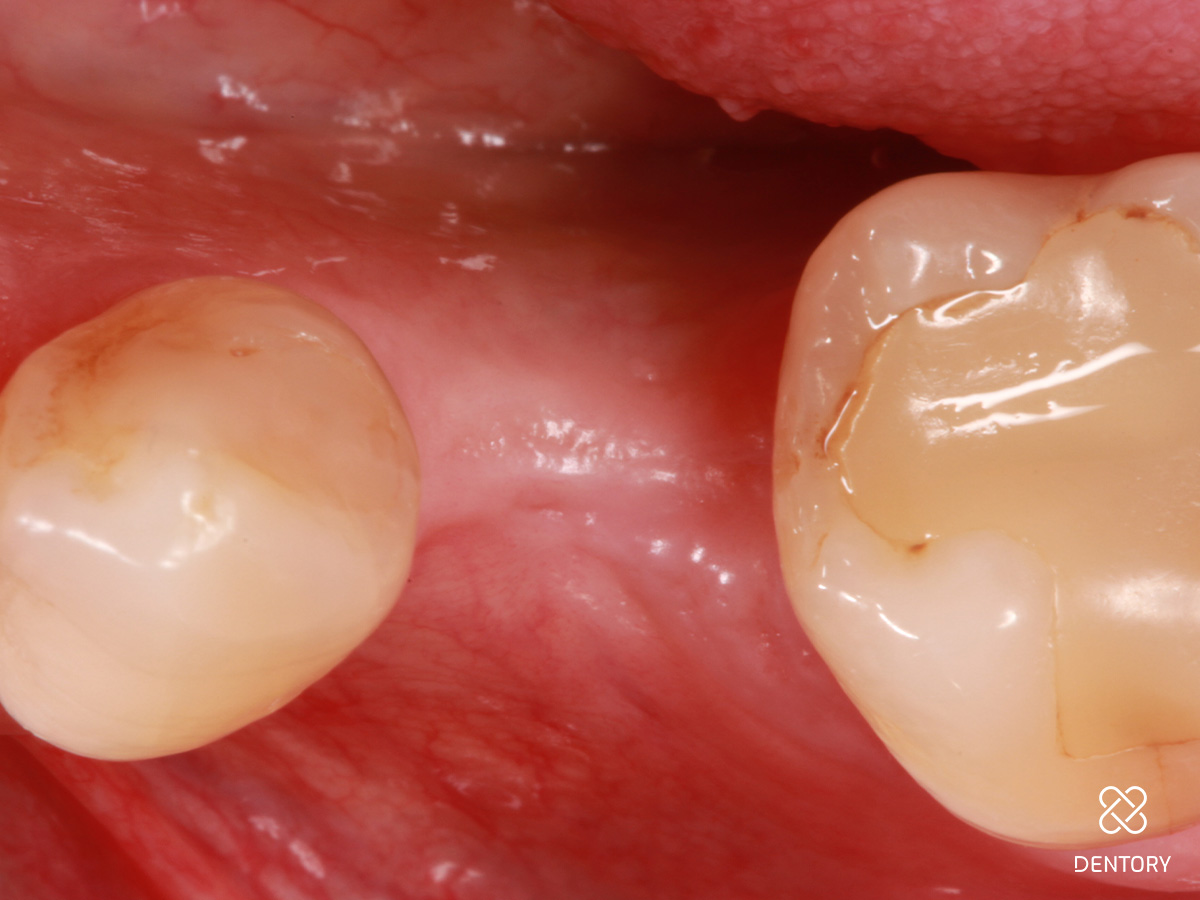

Abbildung 15

Abheilung nach 14 Tagen zum Zeitpunkt der Abformung.